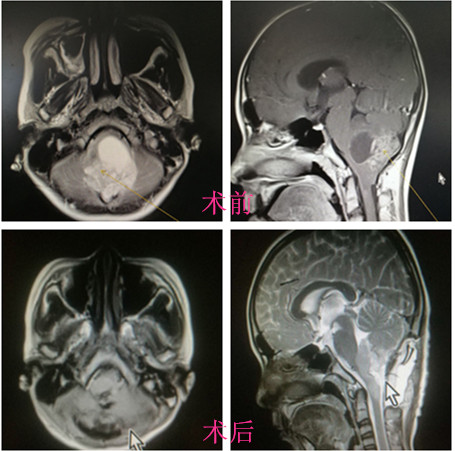

家人带他辗转了几家大医院,医生都认为手术风险太大,不愿接收。感觉前途渺茫的他在家人陪伴下于7月10日来到了湘雅三医院神经外科,专家立即为刘同学安排了住院及核磁共振检查。磁共振检查结果显示在小刘大脑中央的脑干部位生长了一枚土鸡蛋大小的肿瘤,位置很深,与周围组织粘连紧密,孩子的脑干都已经被肿瘤严重压迫,再不采取措施,孩子随时可能陷入昏迷,甚至死亡。

以湘雅三医院神经外科王知非教授为首的专家团队决定手术!在术前制定了严密的手术方案,在神经电生理监测及术中实时肿瘤荧光与血管荧光造影手术显微镜的帮助下,于7月12日历经九个小时的显微镜下手术,成功切除了肿瘤,同时完好地保护了血管和周围正常脑干组织。

术后复查肿瘤全切,患者头痛头晕及行走不稳的症状消失,经过这个暑期的休养,小刘就又可以回到校园重新开始无忧无虑的学习生活了。